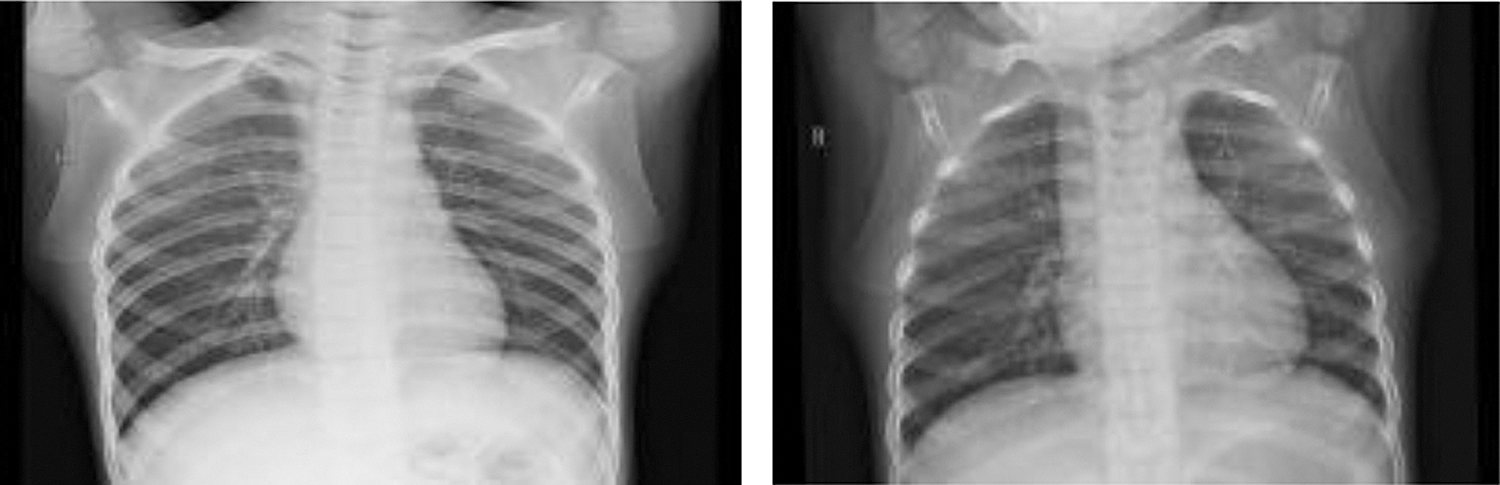

A total of 1000 X-ray images are collected from GitHub and shared by Cohen et al. [33]. There are four classes of images. Among the available images, 250 COVID-19 and 250 normal images are selected. The dataset also includes 250 Pneumonia Viruses and 250 Pneumonia Bacteria for a total of 1000 images. The dataset is balanced due to the fact that each class has 250 images. Fig. 3 shows a sample of the normal and healthy chest X-ray images, while Fig. 4 shows the images of the COVID-19 affected patients.

Figure 3: Chest images of normal and healthy people

Figure 4: Chest X-ray of COVID-19 affected people